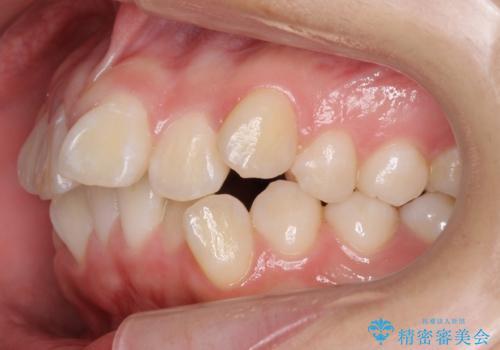

- 前歯のがたがたを主訴に来院。

口元も下げたいとのことでした。